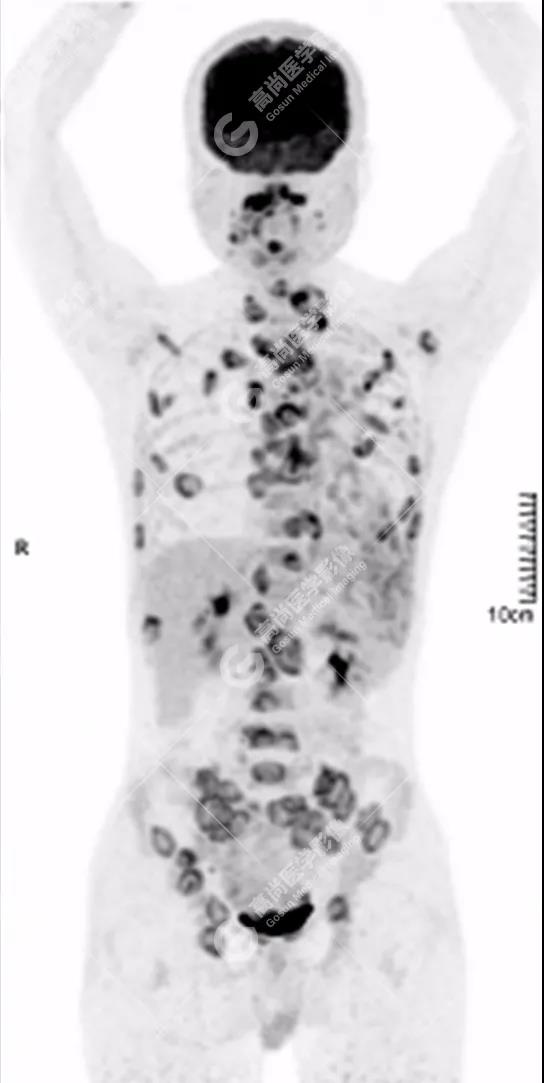

PET/CT全身圖

脊柱多發(fā)椎體及附件骨質(zhì)破壞,代謝不均性增高

全身多處骨質(zhì)破壞,代謝不均性增高

全身多發(fā)高代謝腫大淋巴結(jié),中央代謝缺損

左肺上葉尖后段及下葉背段多發(fā)簇狀斑點(diǎn)狀高代謝灶

左側(cè)胸膜結(jié)節(jié)樣增厚,代謝不同程度增高

雙肺、左側(cè)胸膜多發(fā)結(jié)節(jié)影,全身多處骨質(zhì)破壞,全身多發(fā)淋巴結(jié)腫大,代謝攝取不均勻性增高。